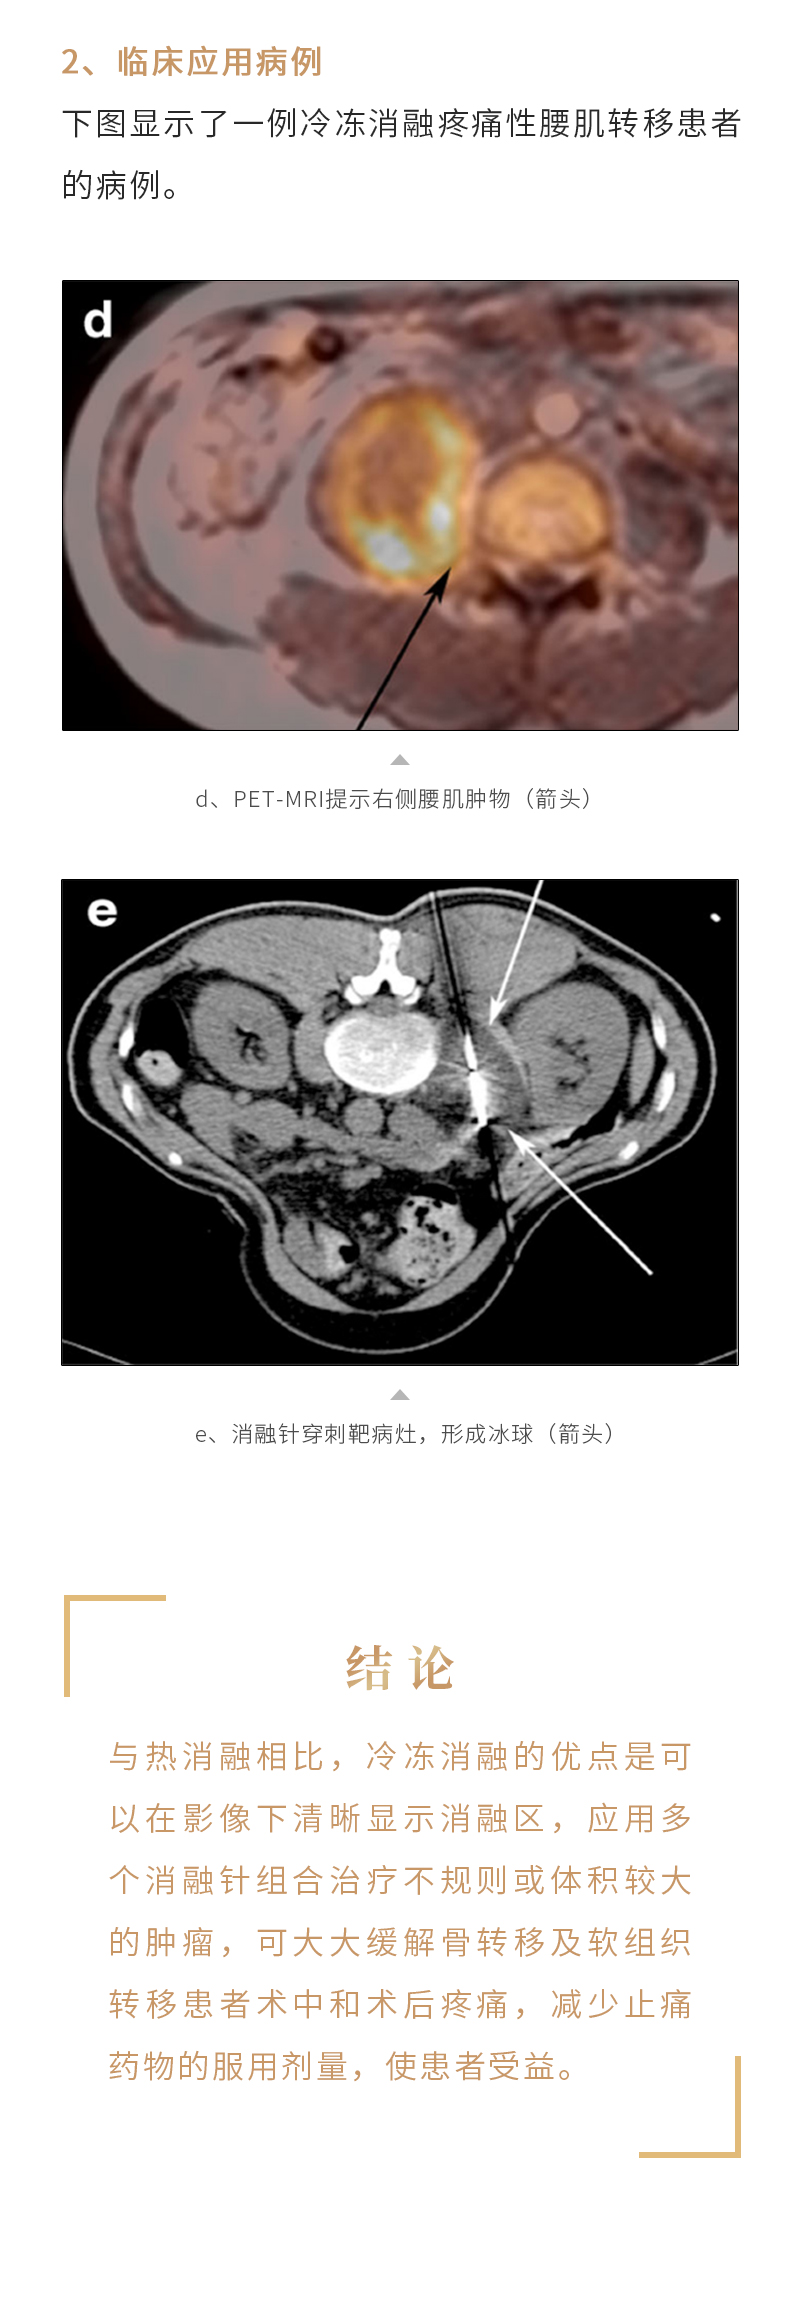

冷冻消融治疗骨与软组织肿瘤——【海杰亚科研资讯】第243期